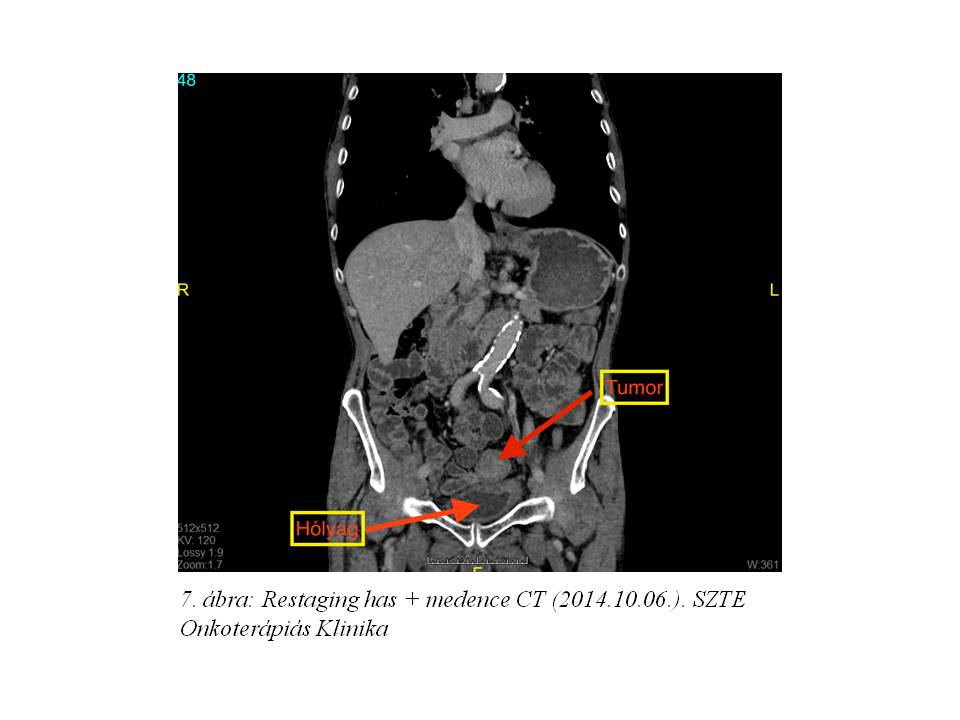

A neoadjuváns-kemoradioterápia sikeres komplettálását követően elvégzett re-staging has+medence CT jó ütemű regressziót igazolt mind az iniciális tumor, mind a nyirokcsomó státusz tekintetében (7. ábra, 8. ábra). Tekintettel a kedvező tumor válaszra 2014.11.05-én SZTE Sebészeti Klinikán sigma resectio és partialis húgyhólyag resectio történt. A szövettani feldolgozás közepesen differenciált cribriformis adenocarcinomát igazolt, ypT3yN0 (0/1 nyirokcsomó) stádiummal. A rezekciós szélek és hólyag nyálkahártyája intaktnak bizonyultak.